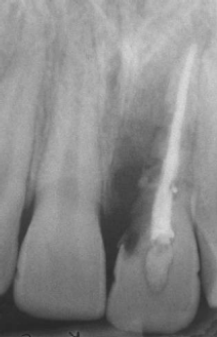

Analise a radiografia periapical a seguir:

Disponível em: Livro – Cirurgia Patologia Oral e Maxilofacial – Neville; Damn; Allen; & Bouquot. 3ª ed.

Assinale a alternativa que corresponde corretamente à condição apresentada pelo elemento dental 21.